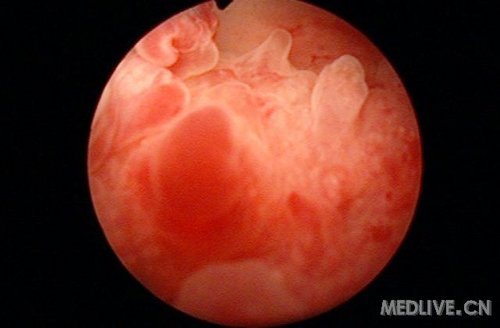

乳头状膀胱炎(图)(膀胱炎|膀胱)